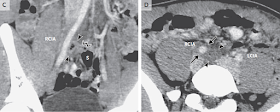

Los estudios de imágenes que habían sido informados

inicialmente como normales fueron revistos y se notó un hallazgo sutil que era

una probable colección extraluminal con aire de 20 por 10 mm, anterior a la

columna vertebral entre el colon sigmoides y la arteria ilíaca común derecha ,

con un engrosamiento adyacente de un segmento corto de la pared arterial (Fig.

1). No había engrosamiento de la pared intestinal, distensión intestinal, ni

diverticulosis colónica; el apéndice no era visible.

Figura 1 Tomografía computarizada del abdomen y

pelvis.

Una imagen axial obtenida a nivel de la pelvis

(Panel A) e imágenes de reconstrucción coronal obtenidas a bajo y gran

magnificación (paneles B y C, respectivamente) muestran una colección contenida,

extraluminal, llena de aire (puntas de flecha) medial a la arteria ilíaca común

derecha (RCIA), con focos de gas lineales adyacentes (punta de flecha doble) que

se extienden al colon sigmoide (S). Una imagen

axial obtenida a nivel del margen superior de la colección (Panel D,

puntas de flecha) muestra densidad de partes blandas adicionales contigua

(flechas) que rodea a la RCIA, un hallazgo que indica inflamación de la pared

arterial En comparación, la arteria ilíaca común izquierda (LCIA) es normal, con

una pared imperceptible. Una imagen de reconstrucción sagital (Panel E) muestra

la colección (puntas de flecha) inmediatamente anteriores al cuerpo vertebral L5 y espacio en disco intervertebral

L5-S1; no hay evidencia de discitis u osteomielitis. En retrospectiva, una

imagen coronal magnificada (Panel F)

muestra una estructura lineal de baja densidad baja densidad (punta de flecha doble) adyacente a la

colección (puntas de flecha) atravesando la RCIA.